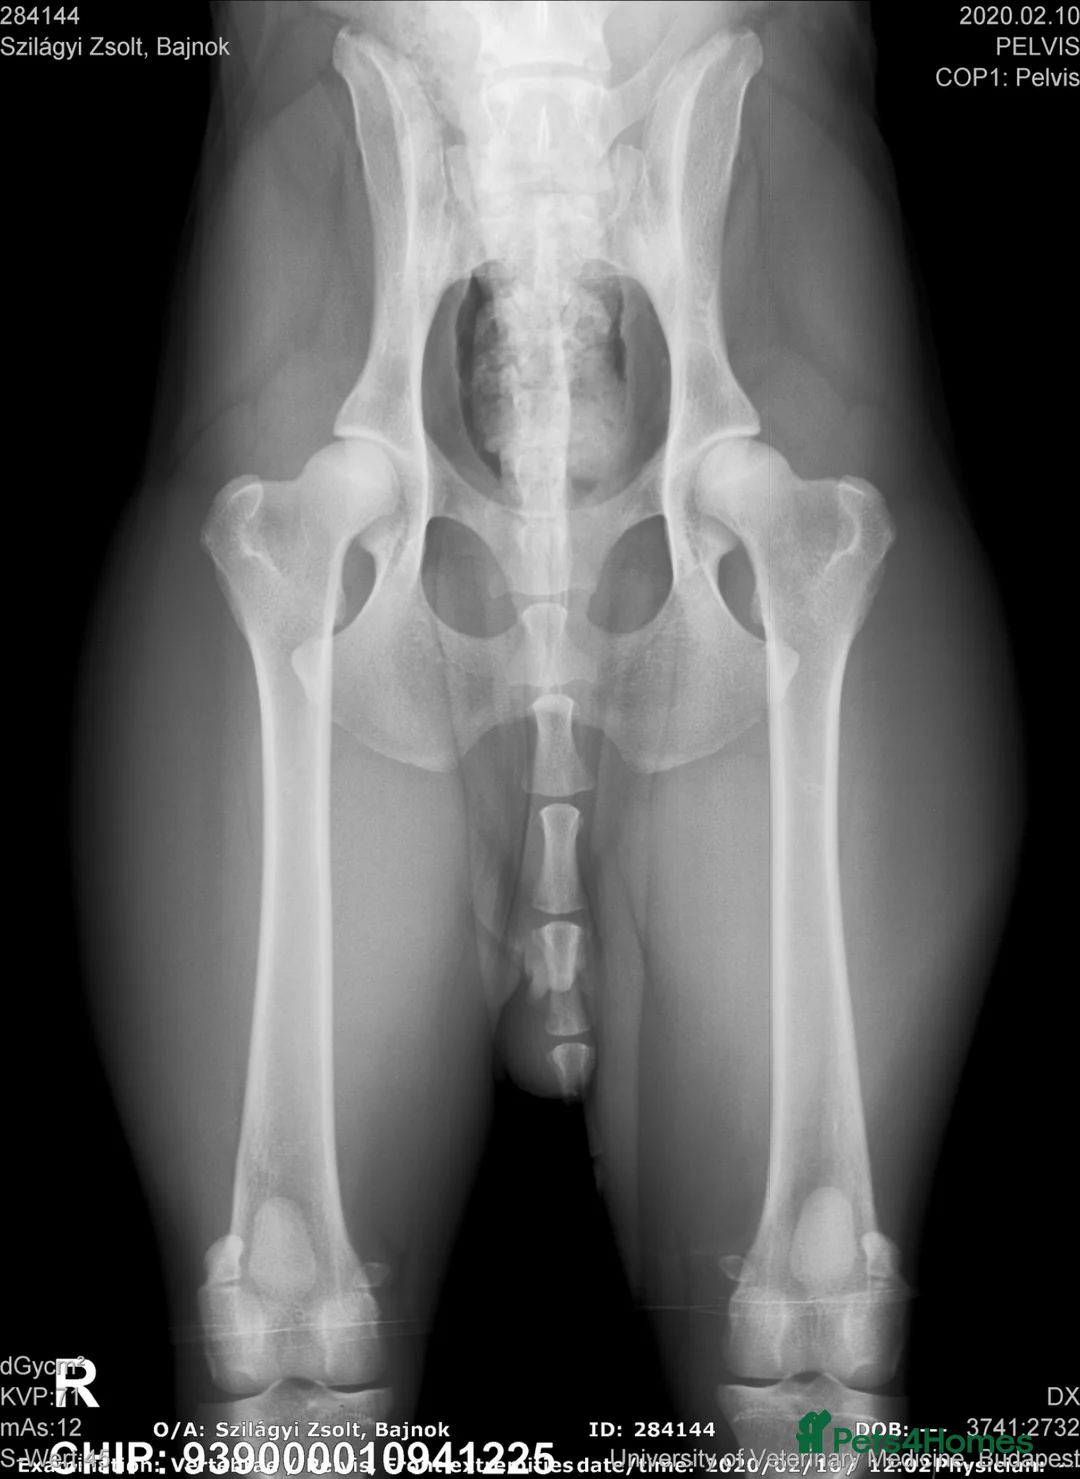

⚜️Maroshegyi Vizslakennel’s⚜️ Update: 3 fantastic Boys ready to mov to the lovely forewer home🏡🐾 vacinated, michrochip, and ful vet chek allredy with 5generations kc certificate and life time guaranty🐾 verywellcome to vizit any time🐾 Https://facebook.com/magyar.gingers.9 "UPDATE: The parents' health tests were conducted at the University of Veterinary Science in Budapest in 2020 and 2022. Documents are updated, X-ray images of the hip joint are available in the photo gallery." We are really happy to announce that we have 8 puppies that were born on 01nd February 2026 From Luxury (Dam) and Bajnok (Sire) who are a very good pairing. The litter is made of 8 beautiful puppies (3 females and 5 males). They are strong, healthy and hold standard characteristics of their species. The puppies are growing well and are socialising early. They are in our loving home and can be viewed with their Mother and Father. These puppies are perfectly suited for competitions and shows due to the parents exceptional characteristics. This is the second litter of Luxury and Bajnok. We followed the development of every puppy of their first litter. They socialise well with children and other animals. We keep connected to their owners by Facebook and WhatsUp groups so we closely follow their health and development. The puppies are very energetic and they require love, time and exercise. Both parents are strongly connected to our family. They have been imported from europe and have multi champion parents that have outstanding properties. Both parents are FCI and KC registered. Sire - Pusztai Pajkos Bajnok (IMP HUN) Bajnok has very special inner and outer characteristics. He is a true leader, does not stop until his task is accomplished and he is temperamental but can be handled well. He is asocial with children and animals; has high load capacity and can be steered well. He has exceptional genetics and his family tree can be traced back to 18 generations with both working and champion ancestors. Dam: Magyar Luxury Leny From Magyar Tim Noah Luxury has been born from a special parigin of two multi champion parents. She has a very elegant appearance, great character, good-natured, wonderful, gentle and loving companion. She walks gracefully on the podium and she takes on her tasks with joy. She is asocial with children and other animals. She has exceptional genetics and her parents have won many awards in the recent years as stated below. Her family characteristics and body build stands out of her species. NOAH MAGYAR-TIM: International Show Champion C.I.E Junior Champion of Poland Junior Champion of Germany Junior Champion of the Netherlands Alpen Champion Champion of Poland Champion of Germany Champion of the Netherlands Champion of Croatia Champion of Belgium AlpenWinner in Germany, Switzerland and Austria Open Champion of Switzerland Open Champion of Austria German Winner 2018, 2019 2 x Golden Winner Belgium 2018 Spring Junior Winner Dortmund 2018 VDH Annual Trophy Winner 2018 Hannover Junior Winner 2018 VDH Europa Junior Winner 2018 Norisieger 2019 Multi BOB, Multi JBOG, Multi BOG, over 40x CACIB Hunting test 1st degree HD-A, ED-0, Eyes clear, Heart clear, L/L free ESPECIAL OF SKYROCKET: European Junior Winner & BOB 2015 Crufts CC & BOB 2017 Vice Junior World Winter 2015 Hungarian Top Vizsla 2019 International Show Champion - C.I.E International Beauty Champion - C.I.B Hungarian Minor Puppy Grand Winner Hungarian Puppy Grand Winner Junior Champion of Hungary Junior Champion of Slovenia Junior Champion of Slovakia Junior Champion of Germany Junior Champion of Austria Champion of Austria Champion of Hungary Champion of Romania Champion Cum Laudae of Romania Champion of Serbia Champion of Slovenia Champion of Slovakia Champion of Croatia Show Champion of Croatia Show Champion of Hungary Show Champion of United Kingdom Grand Champion of Hungary Winter Winner 2016 Karawanken Winner 2016 Alpen Winner 2016 Middle East European Winner 2016 Hungarian Champion of Champion’s Austrian Champion of Champions - Reserve Male Champion of Champions of All Breeds 2016 Austrian Winner 2016 Kvarner Winner 2018 Multi BIS Puppy, BIS Junior, BIS Hunting test 1st degree HD-A, ED-0, Eyes clear, L/L free The puppies are brought up in our home with their parents. They get worms treated every two weeks. They start their potty training when they reach 4 weeks old and at the same time they start socialising with children and other animals. At 6 weeks old, they start their immune strengthening programme and at week 8 they get their immunisation vaccine, microchip and health checks. They can leave to their new loving home when they are 8 weeks old and we can keep them until they reach 10 weeks old if requested. We are looking for loving and energetic families for these lovely puppies that have the required time and energy as well as have some knowledge of this breed. We will create a Facebook or WhatsUp group for the new owners where we will keep contact and provide continuous support. These groups can be used by the owners as well to share pictures and experiences with each other. We would like the owners to join the group so we are able to follow the puppies' health and development. The puppies and their parents can be viewed in Glasgow. alternatively we are happy to do a video call. The puppies will be ready to go to their loving new home on the 31th March when they reach 8 weeks of age. They will leave with 5 generations of KC registration, 5 weeks of KC insurance, mummy scented blanket, their favourite toy, food package and lifetime warranty and support. Please contact us for further information and to book an appointment to view the puppies and their parents. ************ https://www.facebook.com/magyar.gingers.9 Regarding Zsolt from Maroshegyi Vizslakennel’s